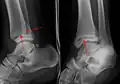

Une fracture triplane de la cheville vue sur une radiographie standard

- Les fractures triplanes, un type particulier de fracture qui implique le squelette immature[13].